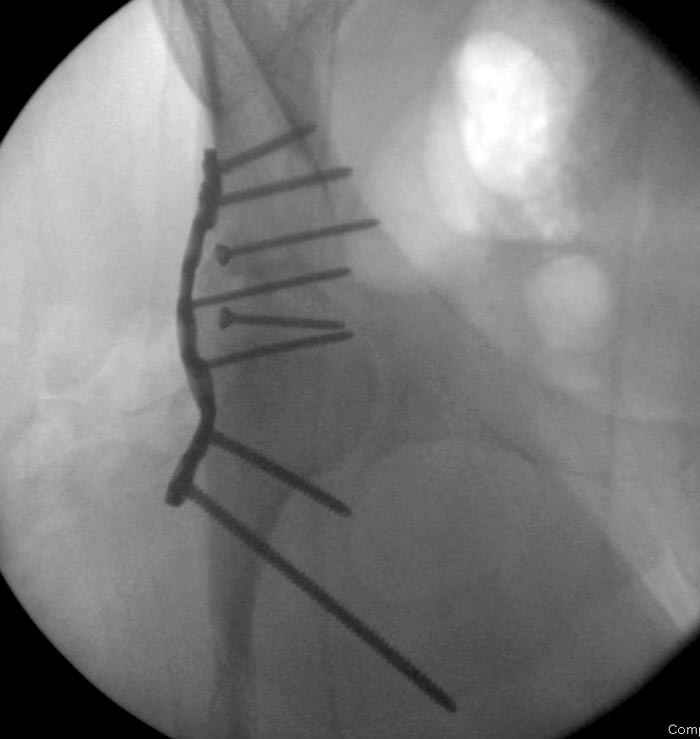

7:30 начало операции, больной на спине, попытка репозиции после анестезии N3, укладка больного на боку, доступ Kocher- Langenbeck, состояние седалищнего нерва около 2.5см кровоподтек, через joistick головка бедра приподнята, освобовождение сустава, фрагмент заднего края более 3х4 см репонирован на свое место. После промывания

сустава, репозиция вывиха (N4), фиксация фрагмента 2.7(4) мм шурупами и допольнительно реконструктивной пластиной на 8 дырок, фиксация 3.5мм шурупами проксимально и дистально.

Интраоперционные N5 косая запирательная и N6 подвздошный снимок

На рисунке N1 предоперационный план лечения ложного сустава шейки бедра- линия ложного сустава, угол и направление введения импланта, клиновидная остеотомия в градусах и миллиметрах, второй снимок после коррекции, расчет, на сколько удлиняется конечность и размеры импланта;

N3 рисунок окончательный снимок, после операции моя рентгенограмма должен выглядеть примерно как эта картина. На N4 снимке клин перед удалением; N5 послеоперации 3 нед.; N6 окончательная рентгенограмма.